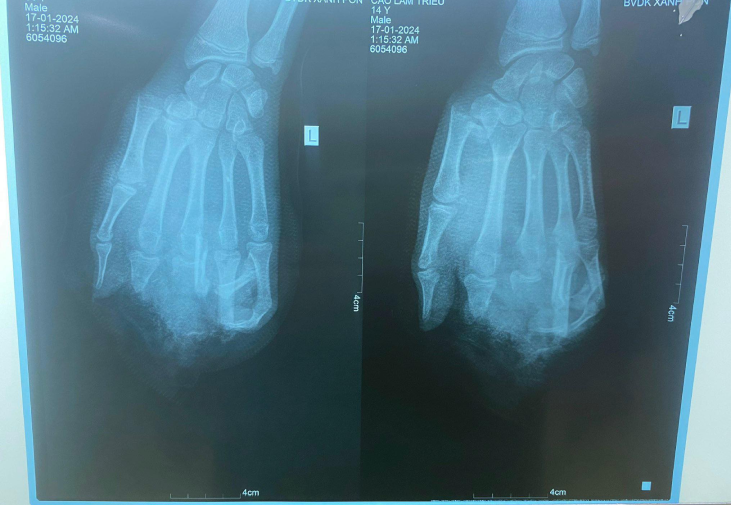

Bệnh nhận C.T.L (14 tuổi, trú tại Hải Dương) được gia đình đưa vào Bệnh viện Đa khoa Xanh Pôn (Hà Nội) cấp cứu trong tình trạng tình trạng dập nát bàn tay trái, gãy xương bàn ngón I, đầu ngón I, V còn hồng.

Theo các bác sĩ, bệnh nhân bị tai nạn trong lúc đang ăn lẩu bằng bếp gas mini. Ngay lập tức, gia đình đã đưa đi nam sinh này đi cấp cứu tại một bệnh viện lớn khác tại Hà Nội và chuyển đến Bệnh viện Đa khoa Xanh Pôn phẫu thuật.

Với tổn thương này, bác sĩ đánh giá vấn đề chức năng bàn tay của bệnh nhân sẽ bị giảm đi rất nhiều, ảnh hưởng lớn đến học tập, sinh hoạt và lao động sau này, đặc biệt còn ảnh hưởng đến tâm lý.